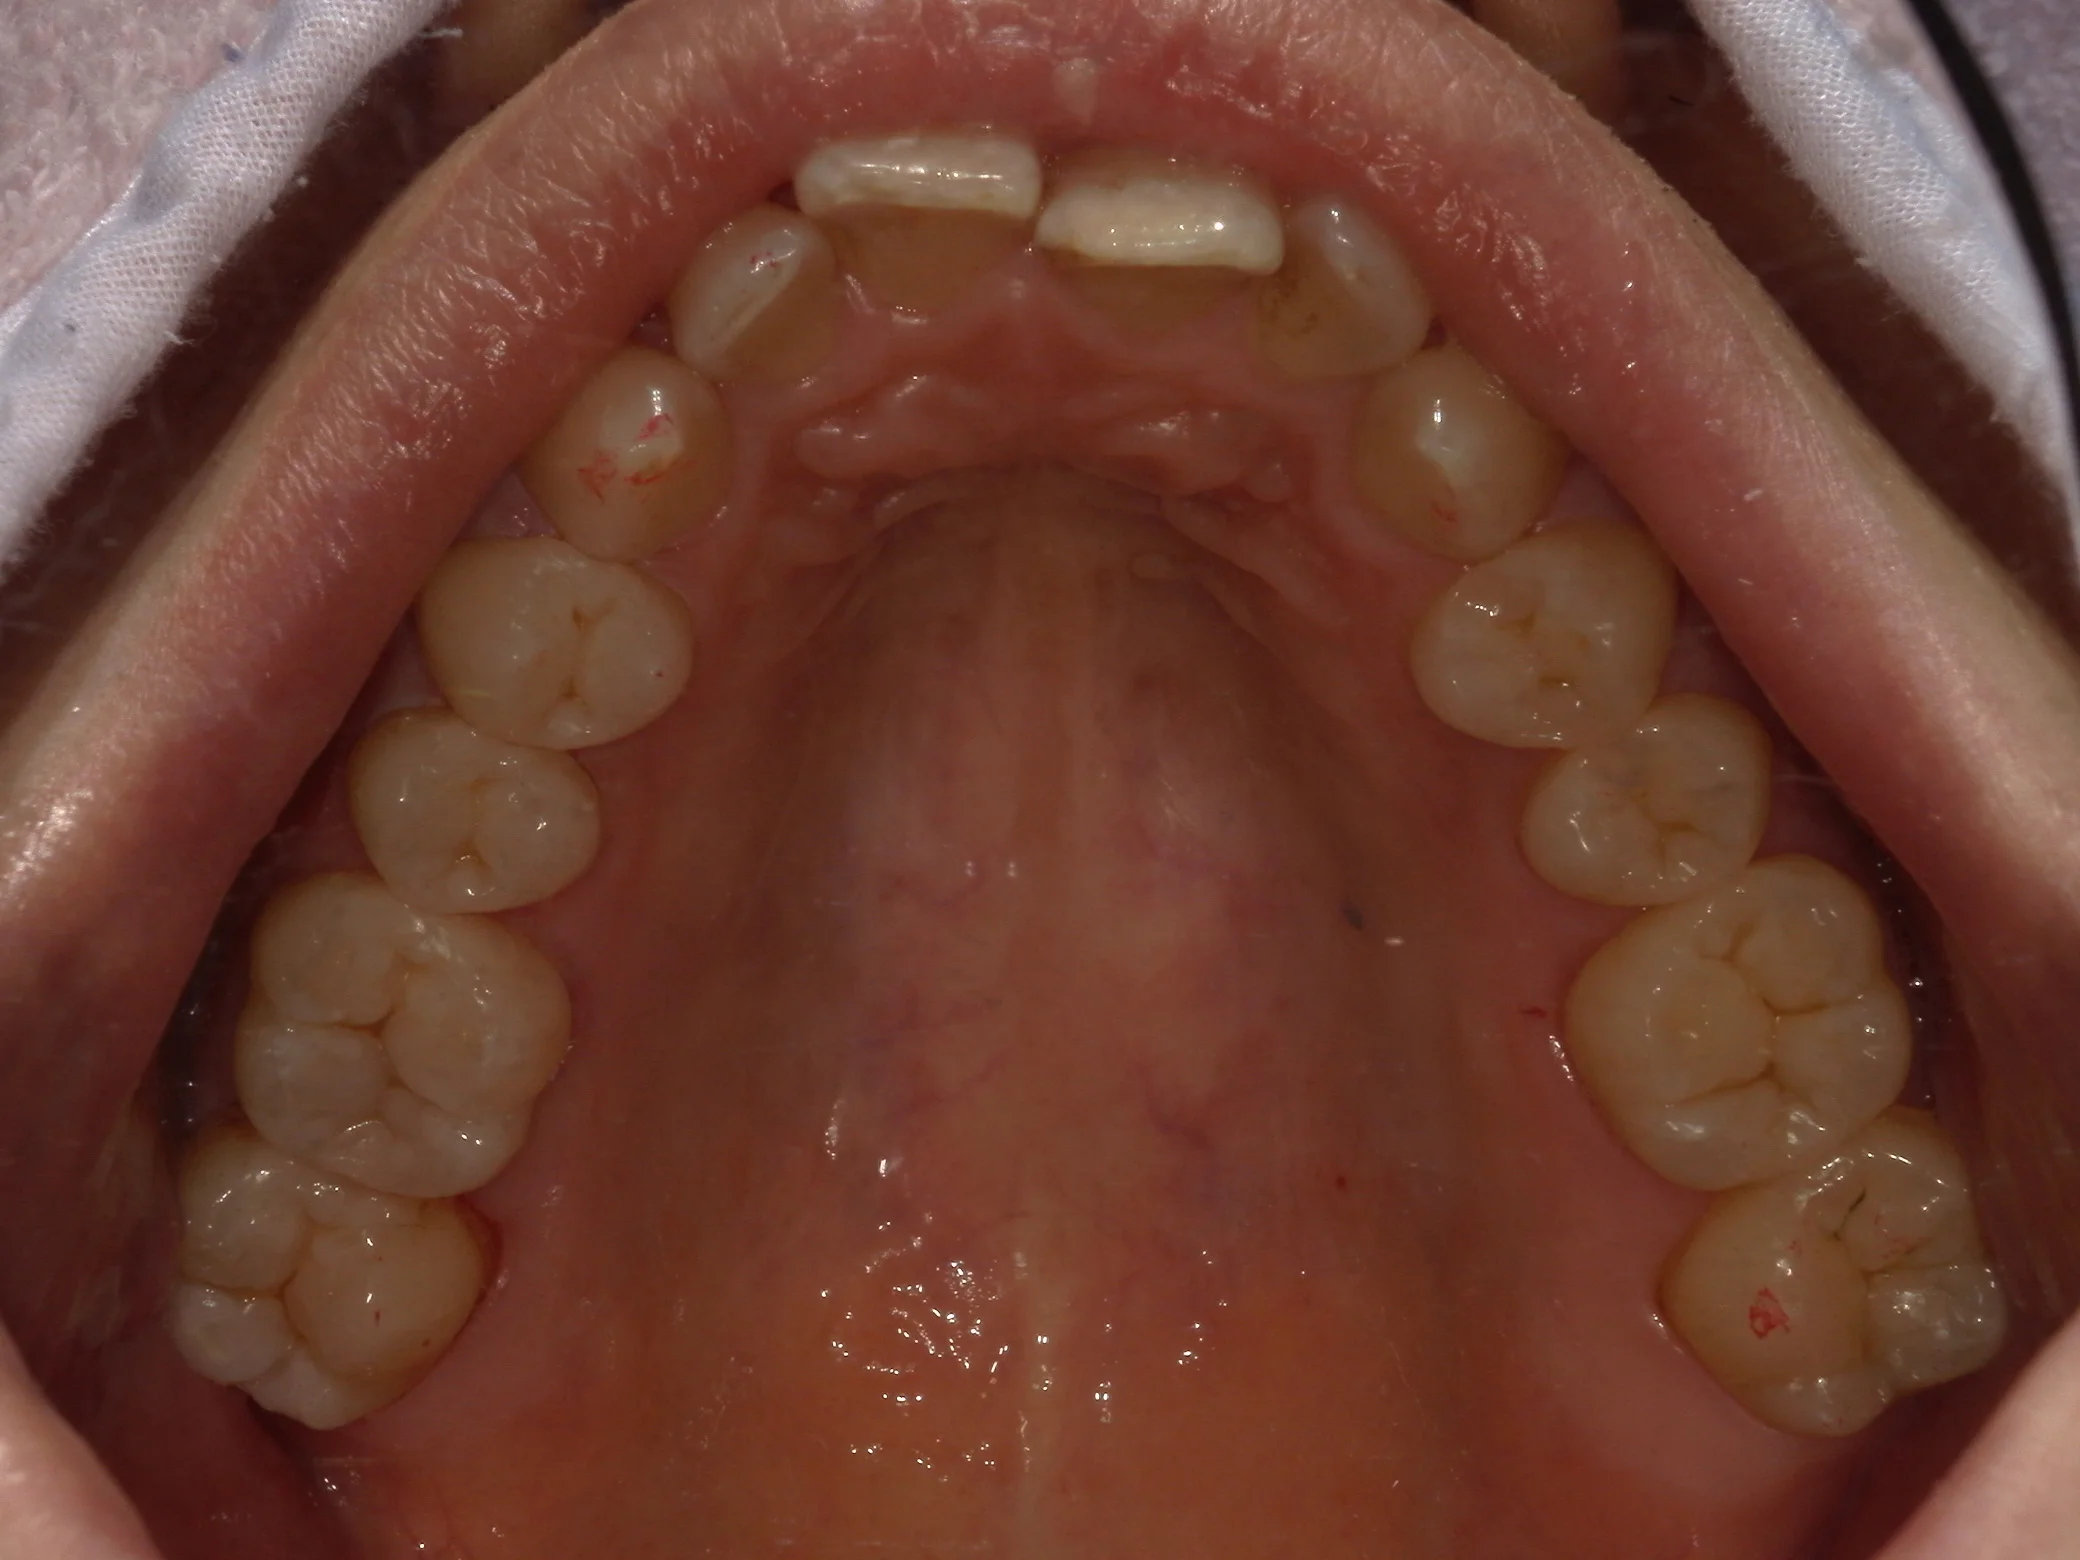

全体が写る写真は術前がこちらで

全体的に金属を白い詰め物に。|坂寄歯科医院(取手市藤代) - 画像5

術後がこちらになります。

全体的に金属を白い詰め物に。|坂寄歯科医院(取手市藤代) - 画像6

金属が一つも無くなり、綺麗に仕上がったかと思います!